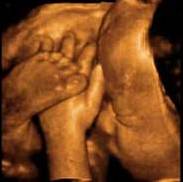

Il bambino ora prende quasi 200 grammi a settimana, pesa circa 1250 grammi e i suoi polmoni continuano ad esercitarsi nella respirazione. La testa cresce per fare spazio al cervello che ogni giorno vede nascere miliardi di nuovi neuroni, scalcia a più non posso ed è possibile contare i suoi movimenti per verificare il suo benessere e controllare che sia ben ossigenato. Per farlo, mettiti sdraiata su un fianco ogni giorno alla stessa ora, rilassati e concentrati su di lui, poi conta quanto tempo occorre al tuo piccolo per farsi sentire almeno dieci volte, conterai calci, pugni, singhiozzi e anche movimenti della testa e del sederino. La buona regola è che non servano più di due ore per arrivare a dieci.

Il bambino continua a crescere e ormai occupa quasi interamente lo spazio nell’utero.È possibile avvertire movimenti netti e precisi, al punto che potresti distinguere bene di quale parte del corpo si tratta, se la testa, il sederino o anche la schiena.